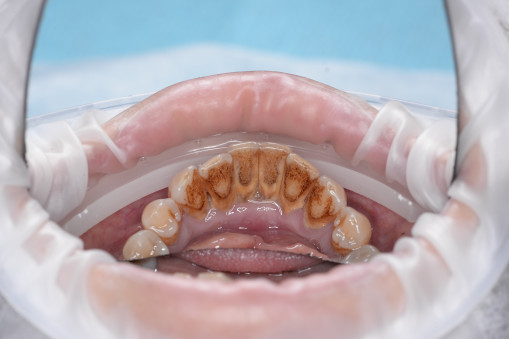

А прежде, чем вы посмотрите фотографии «до» и «после» лечения слизистой оболочки полости рта, проведенных в нашей клинике, хочу поблагодарить большое количество наших пациентов, которые поверили, прониклись нашей концепцией, и мы вместе, именно вместе победили болезни десны, гингивит и пародонтит!

До/после лечения